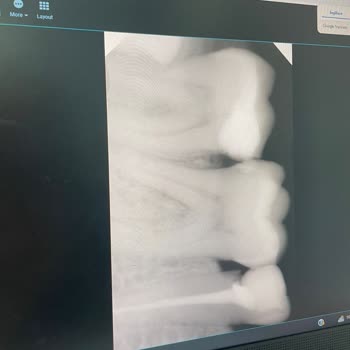

10 Ekim'de saat 9.30'da muayene olduğum Dr. Ö*** A*****, dişime dolgu yaptı. İki gün geçmesine rağmen dolgu yapılan tarafta bir şey yiyemiyorum çünkü ağrı yapıyor. Çok fazla ağrısı yoktu oysa ki ama daha fazla ağrımasın diye doktora gittim. Doktor da durumu iyileştireceğine daha da beter yaptı. Biz ...